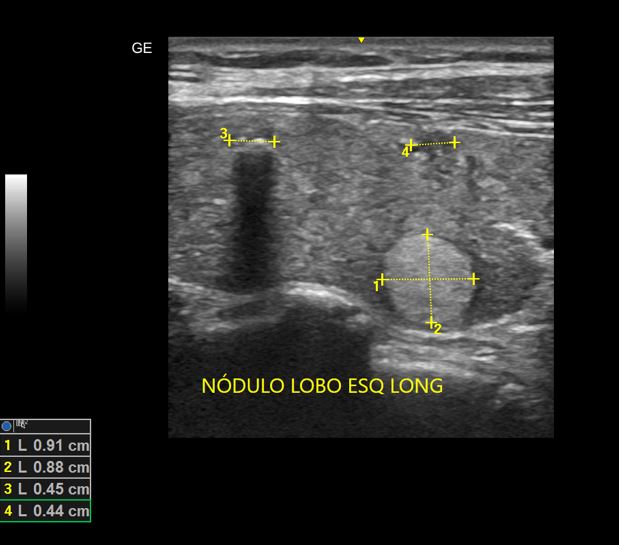

Nódulos de Tireoide

USG de nódulos benignos